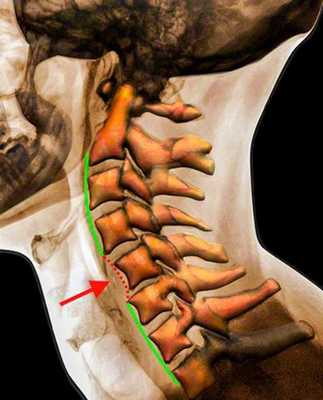

Рентгенограмма. Подвывих в шейном отделе позвоночника. Цветовая обработка изображения.